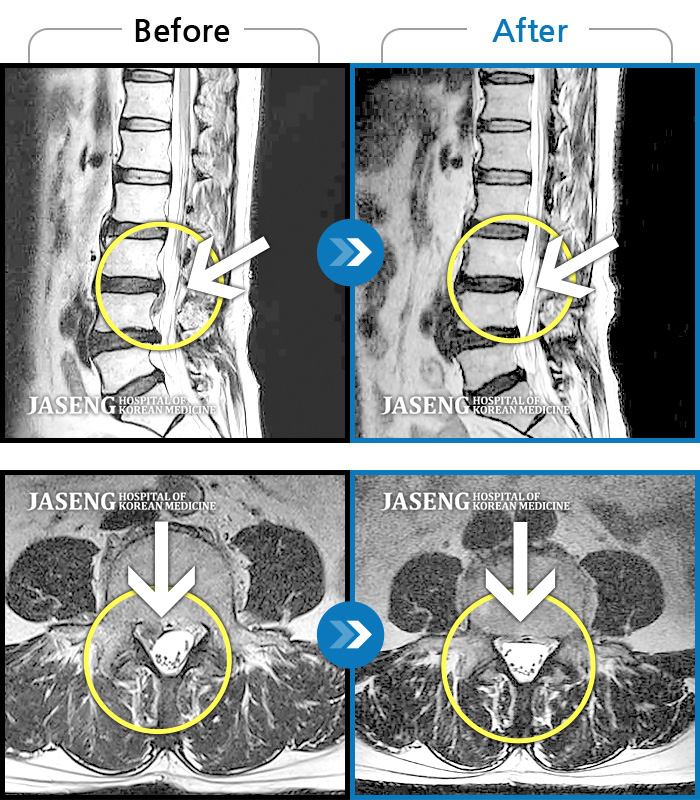

Before

After

환자에게 사전 동의를 받아 동일 조건에서 촬영되었습니다.

개인에 따라 치료 후 부작용이 발생할 수 있으니 의료진과 상담 후 치료를 진행하시기 바랍니다.

허리 및 왼쪽 하지 통증 및 저림

허리 통증과 특히 왼쪽 하지 바깥쪽, 뒤쪽 통증